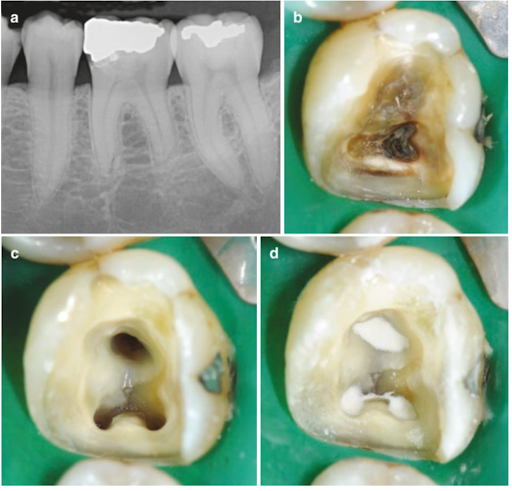

(a) RCL 1 hàm dưới được chẩn đoán viêm tủy có triệu chứng. Phim XQ cho thấy kẽ hở thân răng, vôi hóa buồng tủy và tiêu ngót chóp răng nghiêm trọng. (b) Phần thân răng sau khi đã loại bỏ vật liệu trám và mô răng sâu. (c) Hình ảnh buồng tủy sau khi mở tủy và sửa soạn lối vào. (d) Hình ảnh sau điều trị nội nha, ống tủy được trám bít bằng Ca(OH)2 nguyên chất trộn với nước muối vô trùng để đạt dạng kem.